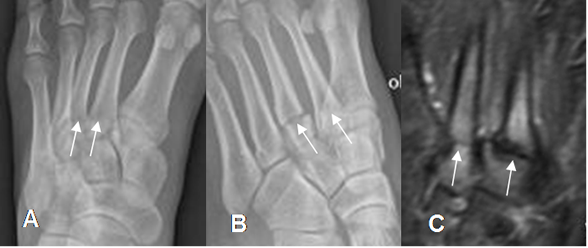

Generalmente los metatarsianos se desplazan posteriormente con o sin fracturas asociadas. (2).(Fig 54, 55 A y B).

Fig 54. Fractura de metatarsianos.

A: Rx AP y B: Rx oblicua. Fracturas no desplazadas en las bases del 2º y 3º

metatarsianos, conservándose la alineación con las cuñas.

C: RM axial en STIR 6 meses después. Fracturas no consolidadas, que hacen sospechar la formación de seudoartrosis.